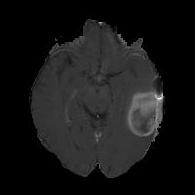

We first introduce a method for connecting the output of a CNN to an ACM, yielding a model for the precise delineation of lesions, to which we refer as Deep Active Lesion Segmentation (DALS) (Figure 4). We then go further to introduce a truly unified framework (Figure 5) that bridges the gap between ACMs and CNNs by leveraging a novel, automatically differentiable level-set ACM with trainable parameters that allows for back-propagation of gradients and can be end-to-end trained along with a backbone CNN from scratch, without any CNN pre-training. The ACM is initialized directly by the CNN and utilizes an energy functional that is locally-tunable by the backbone CNN, through 2D feature maps. Thus, our work overcomes the big hurdle of fully automating the powerful ACM approach to image segmentation. We have applied our proposed framework to the task of building segmentation in aerial images (Figure 6).

(a) Input image (b) DTAC Output (c) (d)